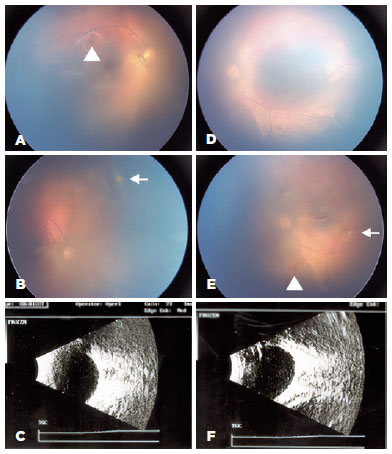

The retina team opted for an expectant management. Six weeks after presentation, there was a decrease of vitreous opacities and preretinal and retinal hemorrhages in both eyes. There was also one cotton wool spot in the superior nasal retinal of OD and one in the temporal equatorial retina of OS. The ultrasound confirmed reduction of vitreous opacities (Figures 2 A-F). Sixteen weeks after admission, there was further improvement of vitreous opacities and macular OCT revealed a preserved foveal contour, with grossly preserved architecture, and normal central subfield thickness (CSFT) for age (206 µm in OD and 211 µm in OS) (Figures 3 A-D).

03-fig02.jpg)